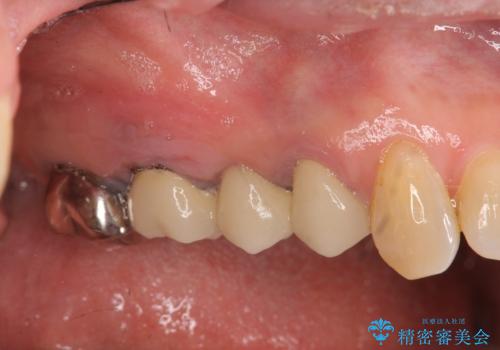

過大な咬合力で破折した奥歯 インプラント治療で咬合機能の回復